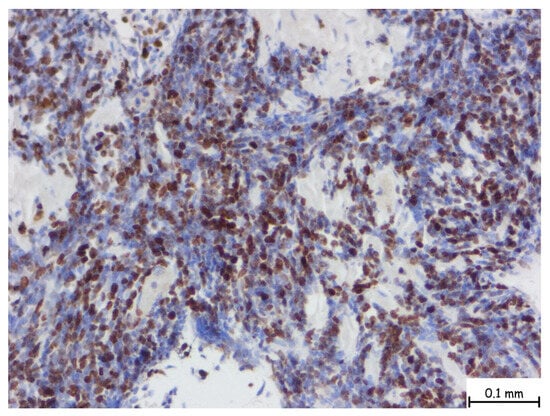

The microscopic examination revealed a lymphoproliferative process characterized by a diffuse lymphoid infiltrate, with focal areas displaying a vaguely nodular structure. The infiltrate consisted of medium-sized cells, among which, large cells with slightly irregular nuclei and no prominent nucleoli were consistently observed. This process involved nearly all examined tissue fragments and disrupted the glandular architecture of the prostatic parenchyma (Figure 2a–d). Immunohistochemical staining with CD20 confirmed a mature B-cell origin (Figure 3). The Ki67 proliferation index was 60–70%. Given the patient’s prior histopathological diagnosis, additional immunohistochemical tests were performed to confirm mantle cell lymphoma, including CD20, CD3, Ki67, Bcl-2, Bcl-6, MUM1, Cyclin D1, CD23, CD5, and CD10. The tumor cells exhibited strong and diffuse expression of Bcl-2, CD5, and Cyclin D1, while CD23, Bcl-6, MUM1, and CD10 were not expressed. This immunophenotype is consistent with mantle cell lymphoma (Figure 4).

Figure 4. The nuclear brown staining pattern is characteristic for Ki-67, a well-established marker of cellular proliferation. In this case, numerous nuclei are positive for Ki-67, indicating a significant fraction of actively cycling cells. The Ki-67 proliferation index is intermediate to high, with an estimated labeling index ranging from 30% to 60% depending on region, suggestive of a more aggressive biological behavior or a higher-grade lymphoma subtype. The microscopic magnification is 40×.